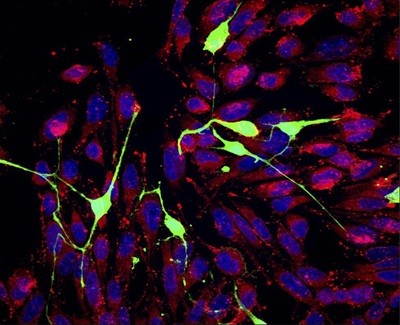

Mitochondria (artist’s impression) wrapped in red-blood-cell membranes can sneak into cells without being tagged for destruction.Credit: Alfred Pasieka/SPL

A well-fitted ‘disguise’ allows transplanted mitochondria to slip into cells whose own mitochondria are defective, scientists reported 18 March in Cell1. Administration of these cloaked mitochondria prolonged the life of mice with a deadly disease caused by abnormal mitochondria.

The scientists found that a mitochondrion wrapped in the membrane of a red blood cell can enter a cell without triggering protective mechanisms that would typically destroy the organelle. The technique “hugely” increased the efficiency of the treatment compared with previous methods, says Mike Devine, a neurobiologist at the Francis Crick Institute in London, who was not involved in the study. The difference is like “night and day”, he says.